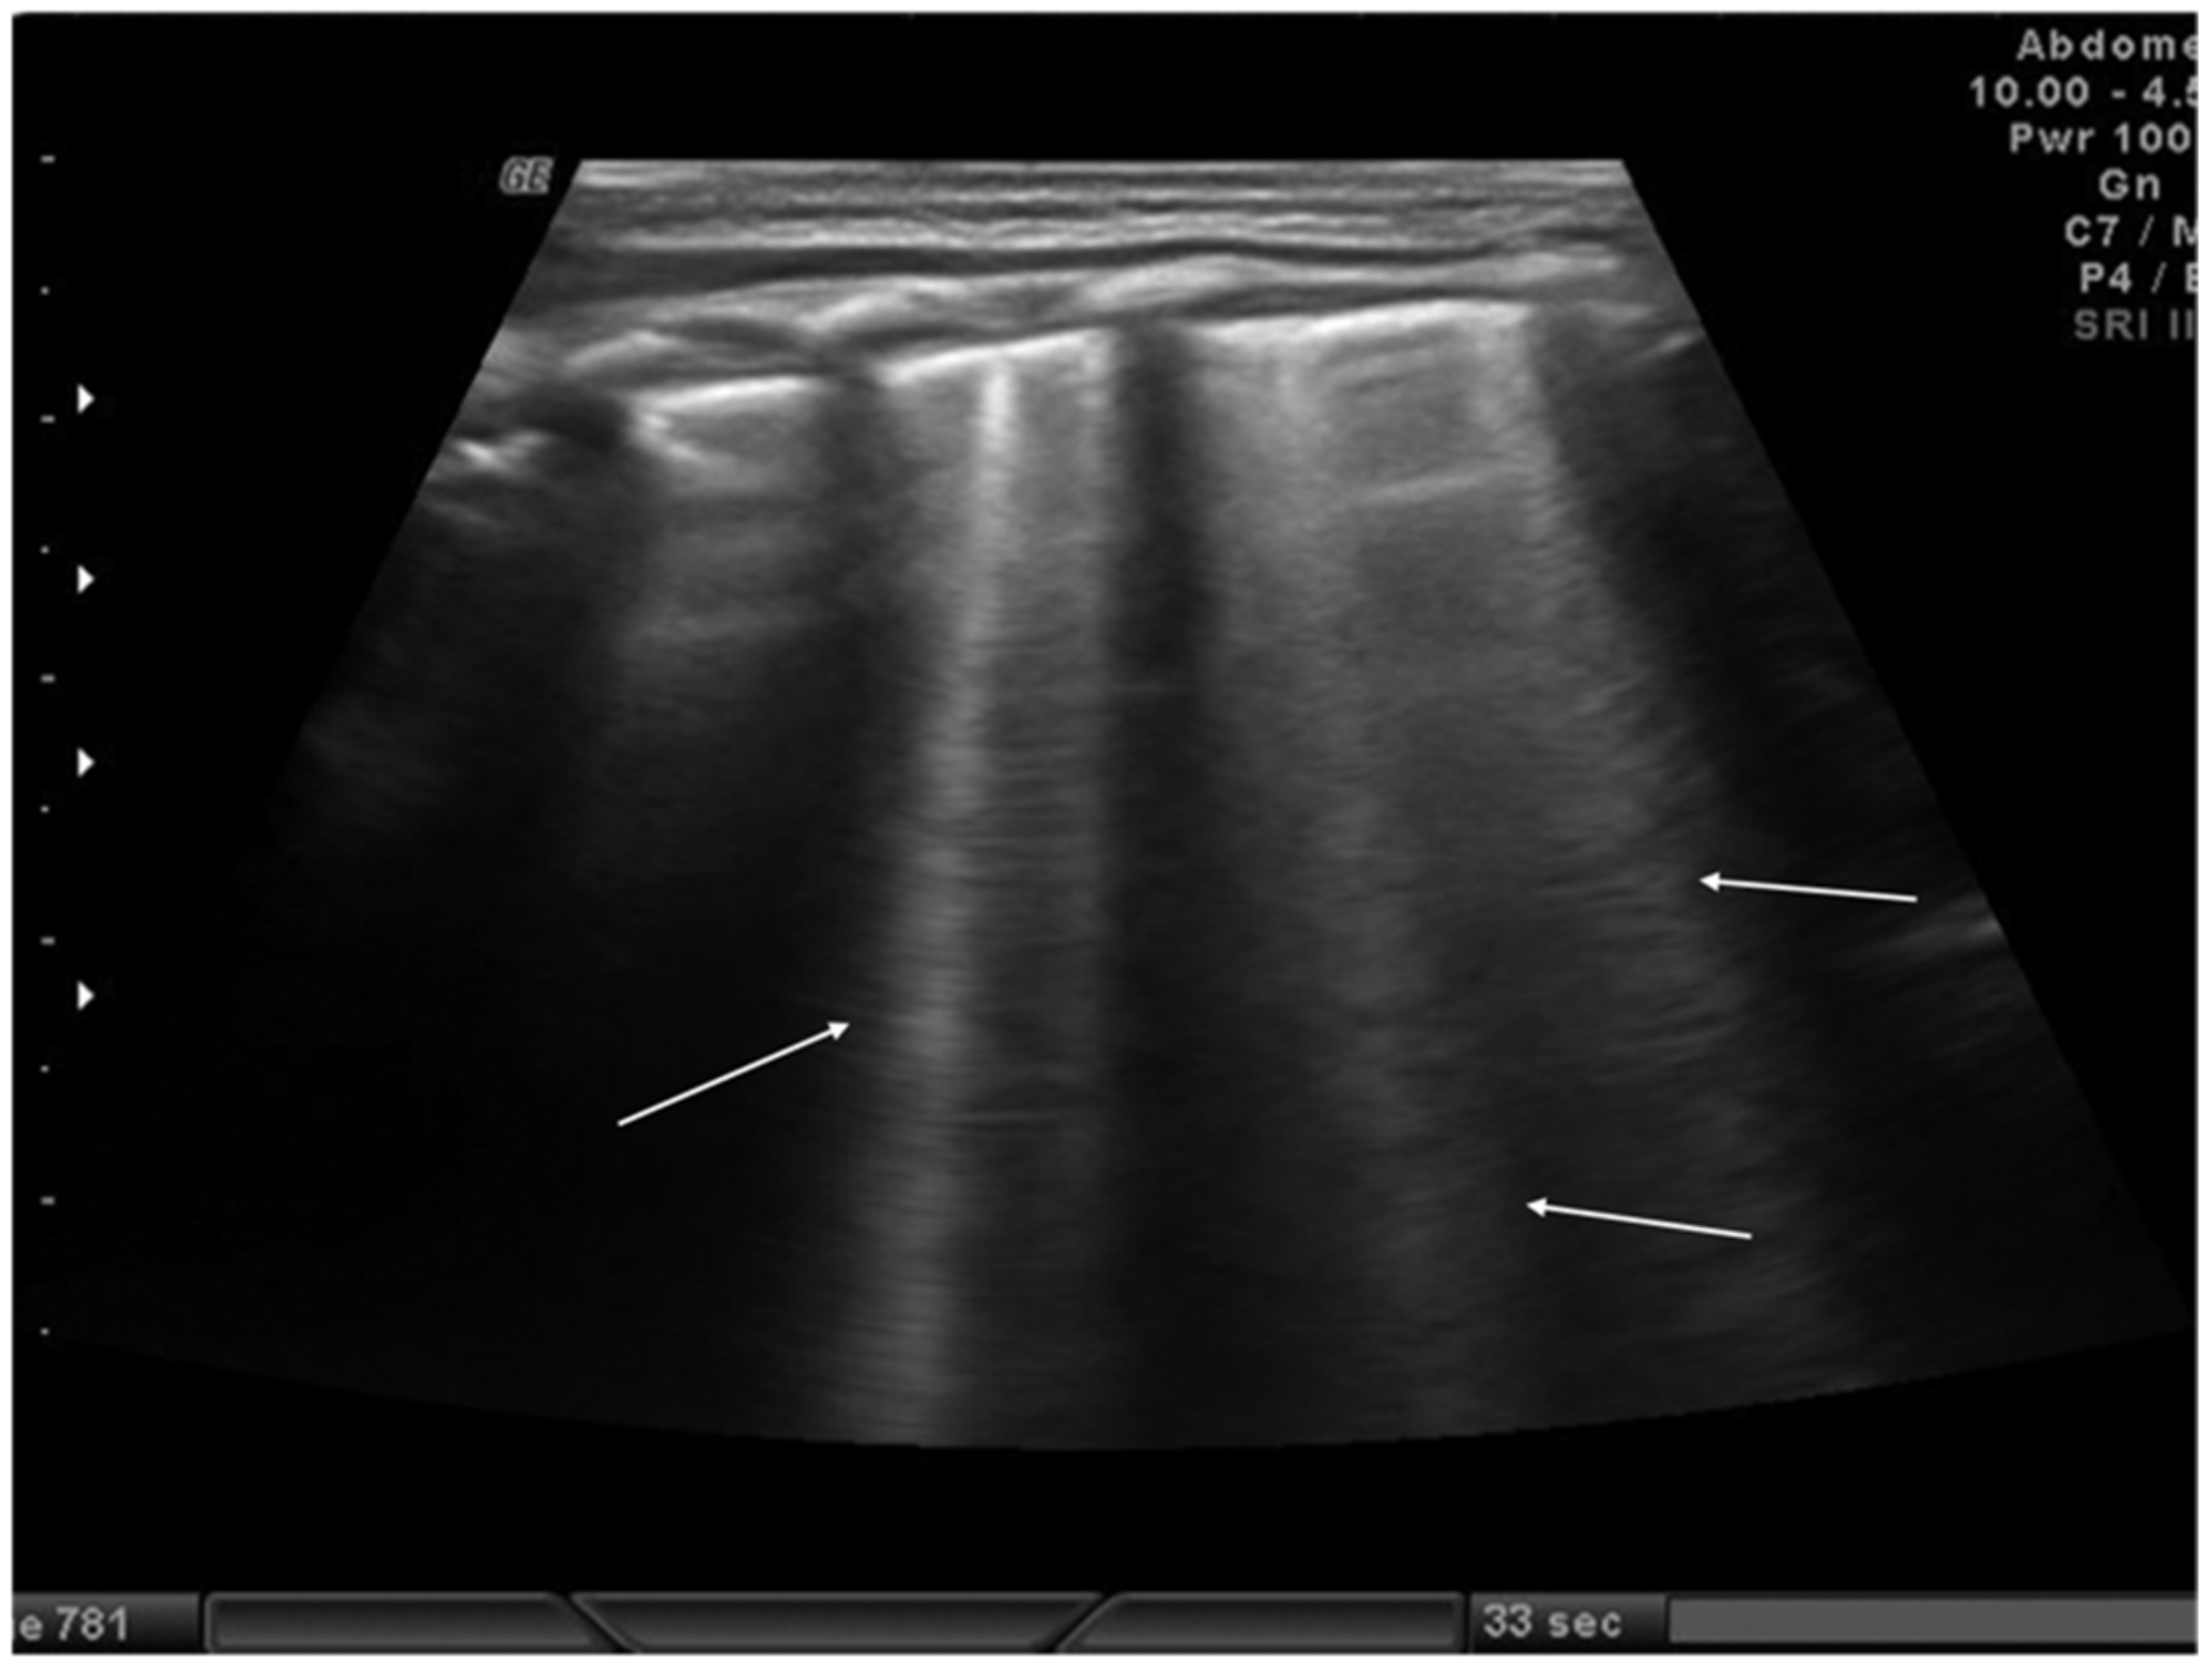

Transient tachypnea of the newborn (TTN), also known as “wet lung,” is caused by a failure in the reabsorption of fluid from the fetal lung. It is typical of term or post-term infants in the case of rapid delivery or cesarean section [24]. Infants with TTN present compact B-lines in the lower lung fields and fewer and less compact B-lines in the upper fields in one or both lungs. These signs, also known as double-lung points, appear because of the greater involvement of the lower lung fields in the disease and are characterized by a sharp ultrasound demarcation line between the upper and lower lung fields of both lungs (Figure 5) [17]. The pleural line is regular, with normal echogenicity and movement with respiratory acts. In contrast to NRDS, no subpleural consolidations are observed. Due to these typical ultrasonographic findings, much evidence has shown how pulmonary ultrasonography can be useful in the early diagnosis of TTN and differentiate TTN from NRDS already by the first hours of life [25].

Figure 5.

Transient tachypnea of the newborn. The dashed line shows the ultrasound demarcation line between the upper and lower lung fields: double-lung point (white arrow).